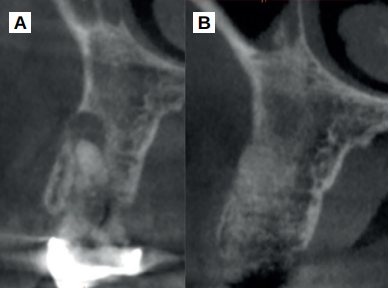

Caso clínico: se presenta el caso clínico de una mujer de 61 años, que acudió a consulta presentando dolor intenso en la zona del segundo premolar superior derecho (1.5). Se realizó la exodoncia del 1.5, usándose como diente donante para realizar una preservación del alveolo tras la extracción. Cuatro meses tras el procedimiento, se colocó un implante y se tomó una biopsia para realizar un análisis histomorfométrico. Un año tras la carga del implante se observaron buenos resultados clínicos y radiográficos.

Clinical case: a 61-year-old woman is presented, who came to private dental clinic presenting intense pain in the area of an upper bicuspid of the first quadrant (1.5). Exodontia of the 1.5 was performed, using it as a donor tooth to obtain the biomaterial to preserve its alveolus. After 4 months re-entry was performed and an implant was placed, harvesting a bone biopsy for histomorphometric analysis. One year post-loading, good clinical and radiographic results were shown.

El comportamiento clínico y radiográfico del diente autólogo ha sido demostrado en diferentes procedimientos de regeneración ósea guiada, elevación de seno maxilar y procedimientos de preservación alveolar12-16. En una reciente revisión sistemática, realizada en 202217, se ha demostrado que se trata de un material que consigue una mayor reducción de las dimensiones óseas cuando se emplea en preservación alveolar tras las extracciones y mejores resultados histomorfométricos en comparación con otros sustitutos óseos, como xenoinjertos y aloinjertos.